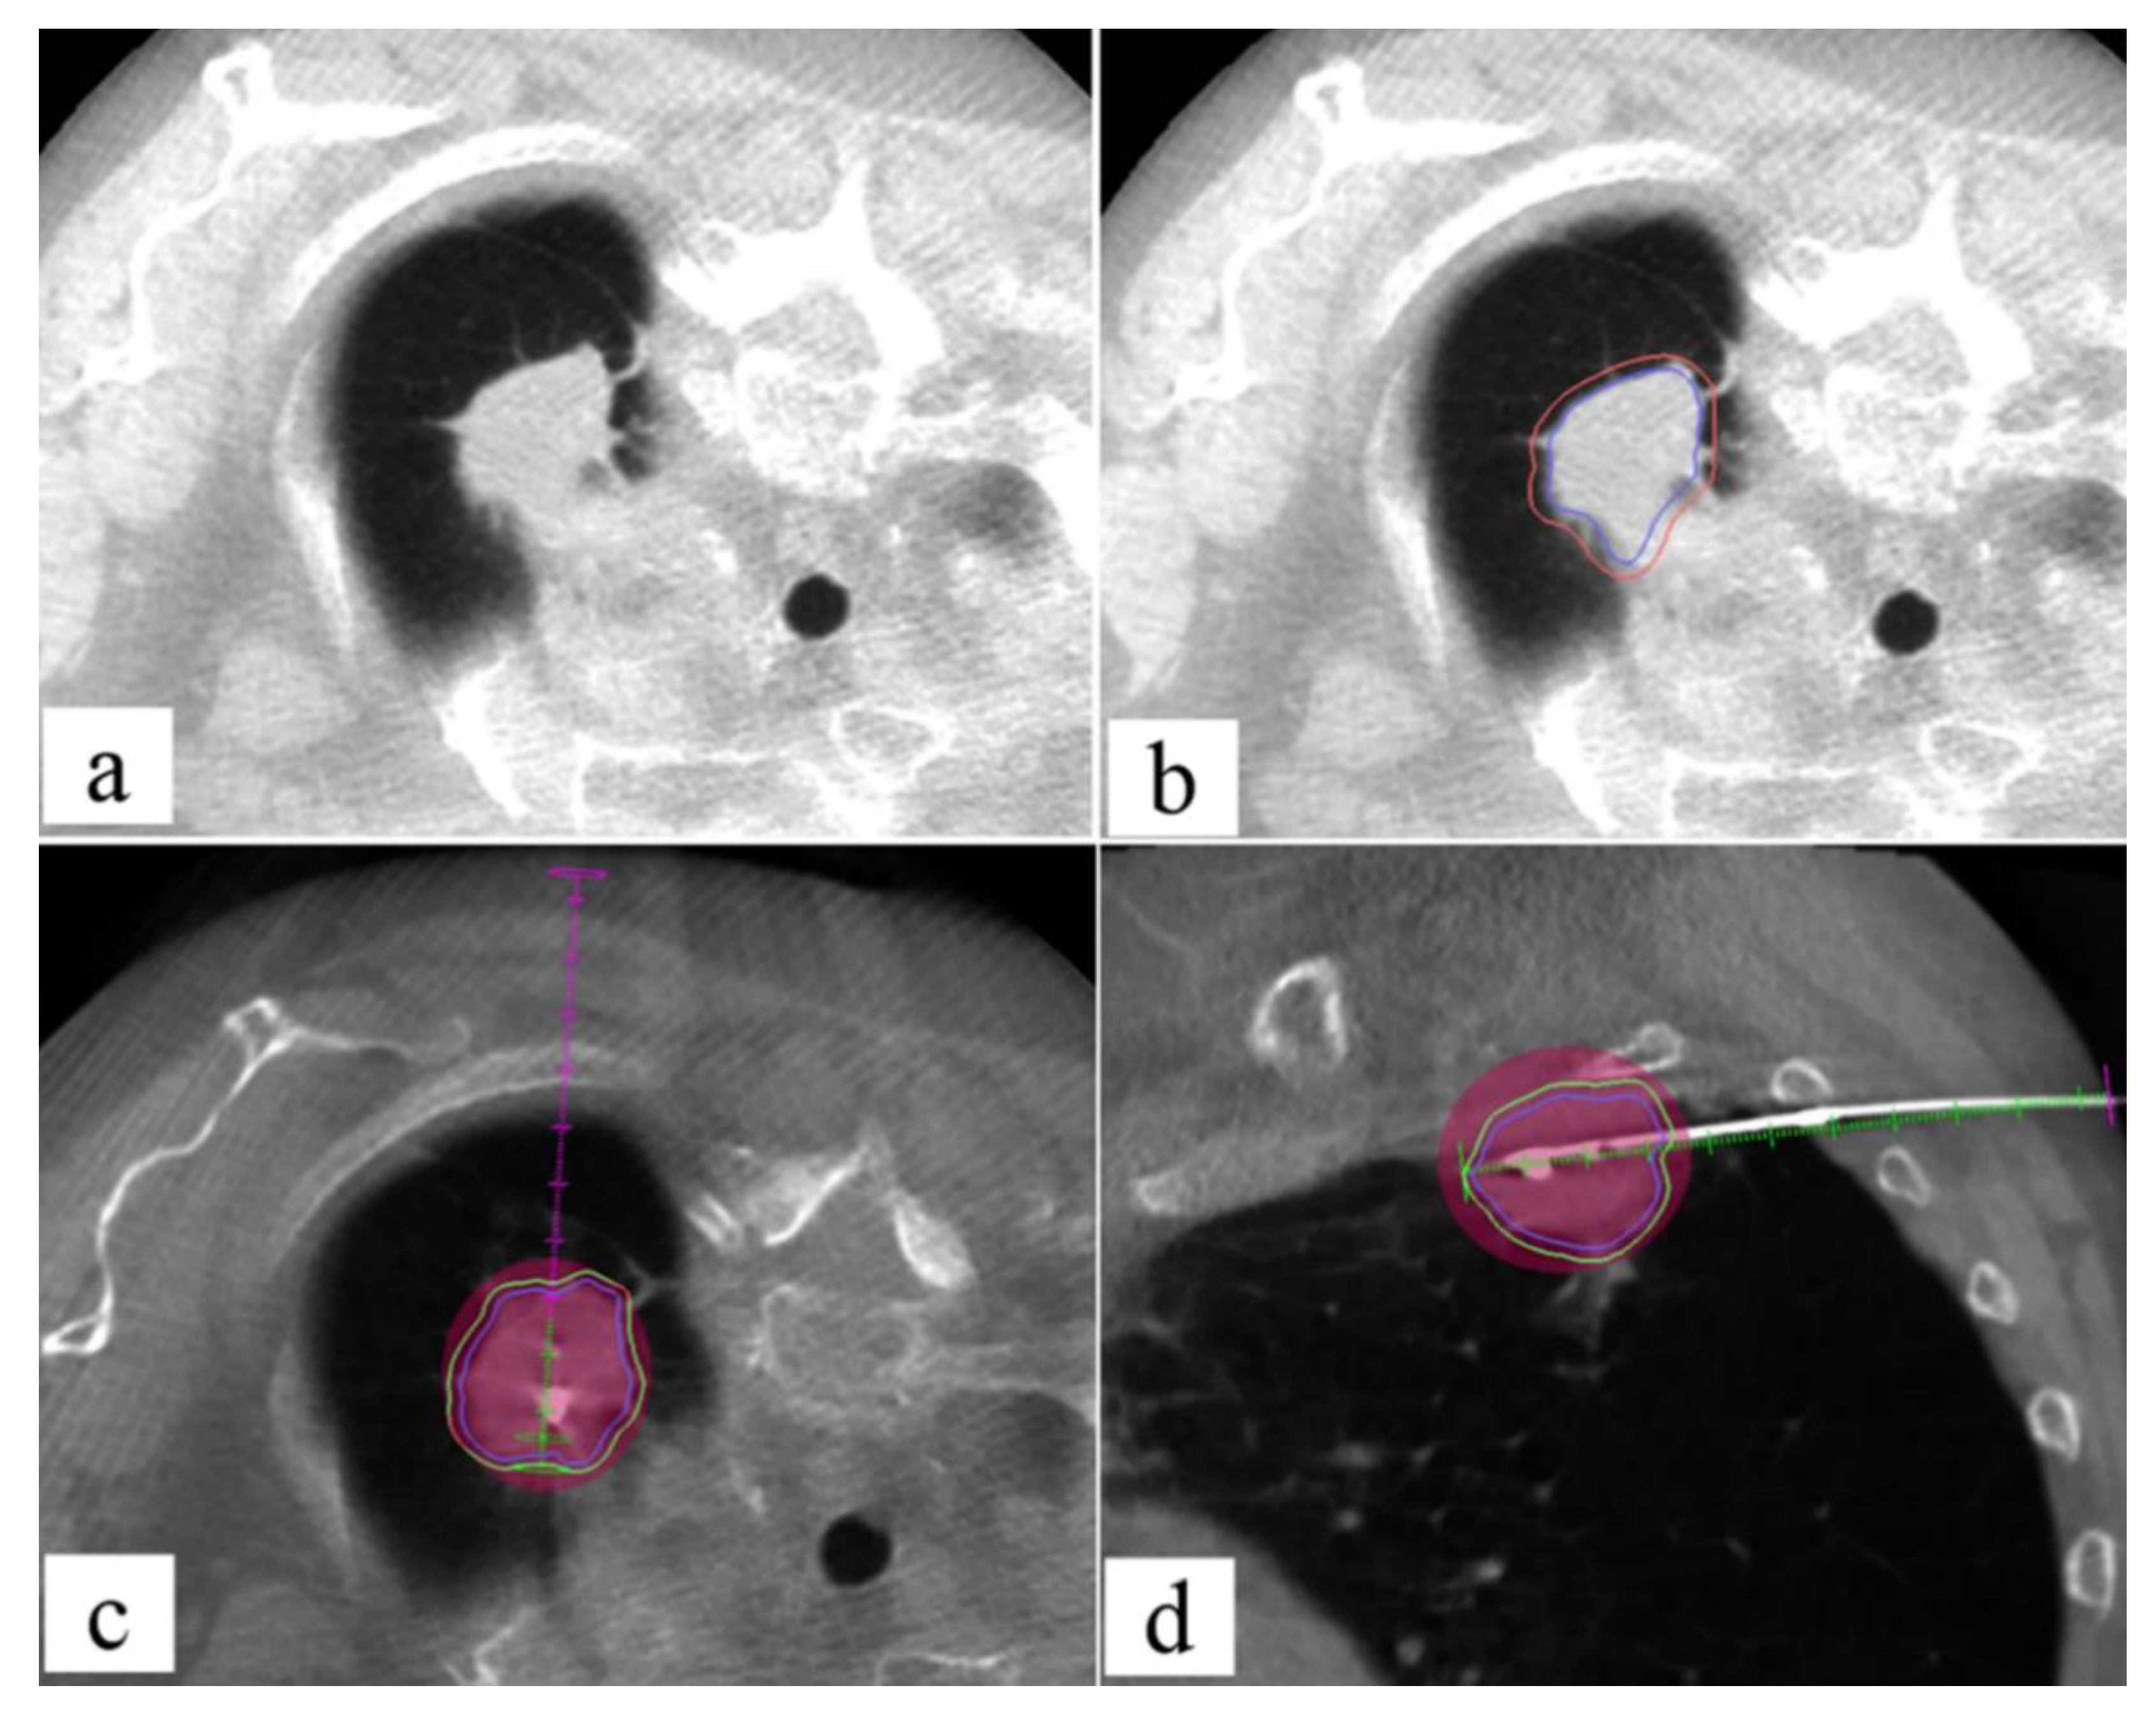

- De Marini, P.; Cazzato, R.L.; Garnon, J.; Shaygi, B.; Koch, G.; Auloge, P.; Tricard, T.; Lang, H.; Gangi, A. Percutaneous MR-Guided Prostate Cancer Cryoablation Technical Updates and Literature Review. BJR Open 2019, 1, 20180043. [Google Scholar] [CrossRef] [PubMed]

- De Marini, P.; Cazzato, R.L.; Garnon, J.; Dalili, D.; Leonard-Lorant, I.; Leclerc, L.; Autrusseau, P.-A.; Auloge, P.; Weiss, J.; Tricard, T.; et al. Safety and Oncologic Efficacy of Percutaneous MRI-Guided Cryoablation of Intraparenchymal Renal Cancers. Diagn. Interv. Imaging 2021, 102, 531–538. [Google Scholar] [CrossRef]

- Cazzato, R.L.; De Marini, P.; Auloge, P.; Leclerc, L.; Tricard, T.; Linder, V.; Jost, M.; Ramamurthy, N.; Lang, H.; Garnon, J.; et al. Diagnostic Accuracy and Safety of Percutaneous MRI-Guided Biopsy of Solid Renal Masses: Single-Center Results after 4.5 Years. Eur. Radiol. 2021, 31, 580–590. [Google Scholar] [CrossRef]